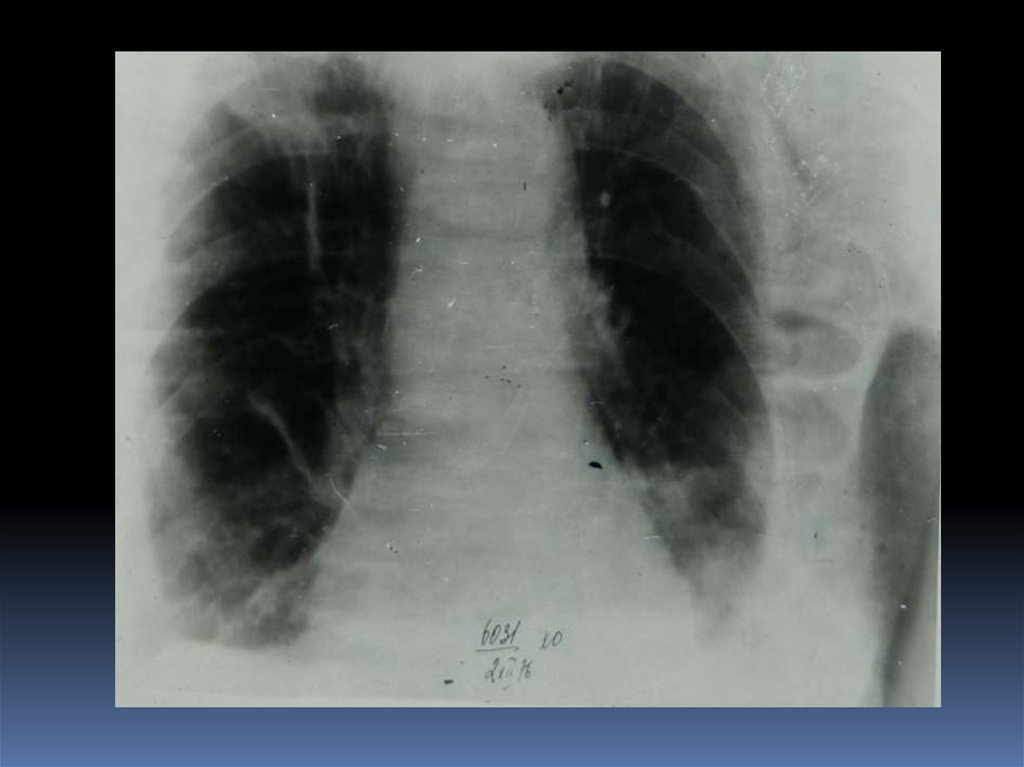

5. Проведение рентгеноскопического исследования раненого.

6. Проведение рентгенографического исследования раненого.

7. Виды травматического повреждения грудной клетки:

пневмоторакс;

гемоторакс;

гемопневмоторакс;

внутрилегочные гематомы;

дисковидные ателектазы;

посттравматические пневмонии.